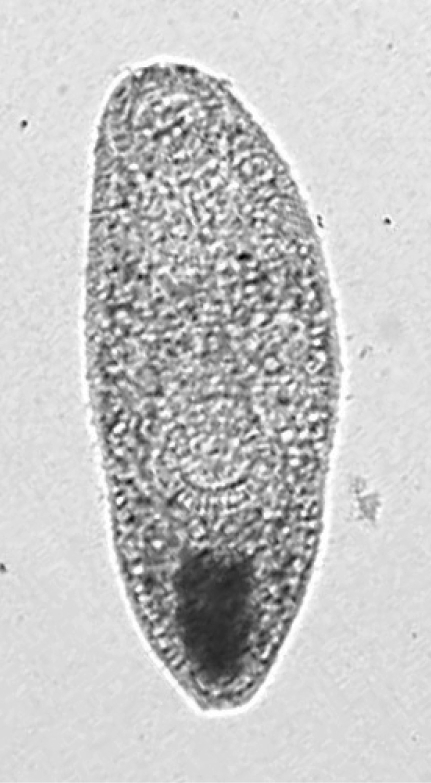

Fig. 3

An excysted Opisthtorchis metacercaria. × 100.

kjp-45-45-g003.jpg

Prevalence of metacercariae in wild fish collected at markets

The results from this study extend our understanding on the geographic distribution of zoonotic liver and intestinal FZTs in Vietnam, and in Asia. The examination of cultured and wild fish collected in An Giang province revealed the presence of O. viverrini and, for the first time in Vietnam, 2 species of intestinal flukes, i.e., H. pumilio and Procerovum sp. The identification of the recovered Opisthtorchis metacercariae as O. viverrini is provisional, because it was not possible to infect laboratory animals for adult worm recovery, a stage which can provide conclusive morphological features for identification. Also, other non-zoonotic species of the genus are reported in Vietnam (Yamaguti 1971), and could be present in fish. However, we feel this identification is likely, because of the lack of evidence for other species in the Mekong Delta region. Yamaguti (1971) accepted 18 species of Opisthtorchis from mammals, birds and fishes, but only 2 of these, O. viverrini and O. felineus, were recorded from Southeast Asia; the latter, however, is not currently considered endemic to Southeast Asia (Kwaekes, 2003). Two species have been reported from China, one from a bird and one from fish, but little is known or reported on these since the 1940s. The identification, of metacercariae recovered in this study as O. viverrini, is supported by the morphological features of the metacercariae (Figs. 3 and 4), and the numerous reports on the presence of this species in humans and fish in South East Asia (De et al., 2003; Chai et al., 2005a, b; Scholtz et al., 1991). It is proposed that this identification be regarded as provisional, however, until the metacercariae are again found and studies such as adult worm examinations (by animal infection studies) can be carried out to confirm this identification.